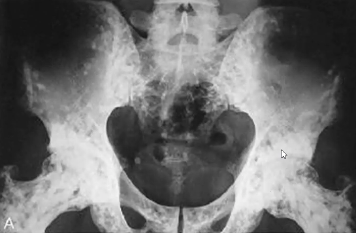

Tumeur à cell géante (ostéoclastome) : 80% bénin 20% Malin

- 20-40 ans

- Prompt à fx patho

- Touche les os longs, subarticulaire, près plateau physe, soap bubble apparence

- « Soap bubble appearance », plusieurs compartiments

- Bien défini, petite zone de transition (bénin)

- Moins bien défini et longue zone de transition (malin)

- Distal radius ++ (malin)

- Risque de tourner en ostéosarcome